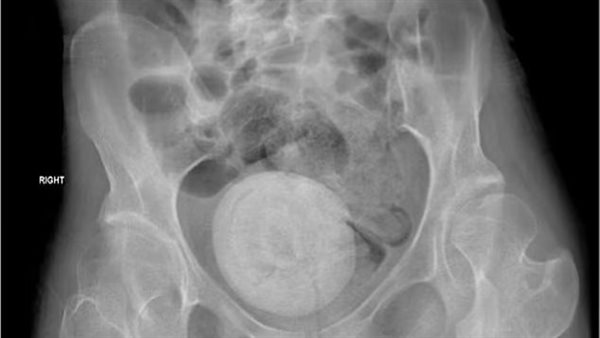

حالة طبية نادرة.. اكتشاف حصوة مهبلية بحجم برتقالة كبيرة في حوض امرأة

حصوة بحجم البرتقالة

وقال الأطباء إنها بدت شاحبة وخاملة، وتم إجراء أشعة مقطعية على بطنها وحوضها، وأظهرت الصور كتلة مستديرة كبيرة في منطقة الحوض، بحجم البرتقالة.